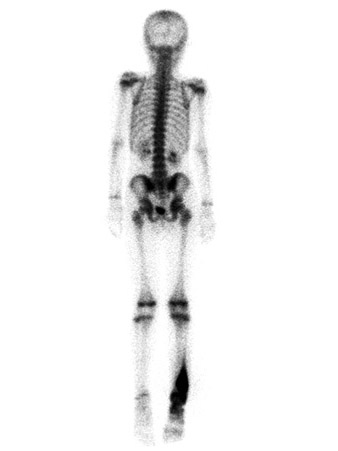

На этой остеосцинтиграмме (вид сзади) определяется повышенное накопление радиоизотопа в правой голени подростка, что характерно для активно растущей опухоли кости. Вид симметричных областей накоплений в коленных, плечевых и запястных суставах типичен для нормального развития скелета

David A. Rubin, MD, Сент-Луис, Миссури, США